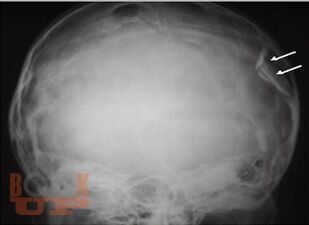

В учебном пособии представлены современные взгляды на вопросы этиологии, патогенеза, диагностики и оперативного лечения черепно-мозговой травмы у детей.